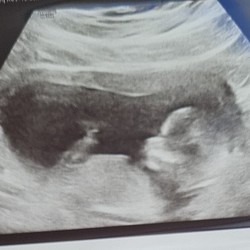

First Pregnancy Scan After Ivf In Vitro Fertilization Treatment Forum Instituto Bernabeu

Eerste Echo Na Icsi Spannend Zwangerschapspraat 24baby Nl Forum